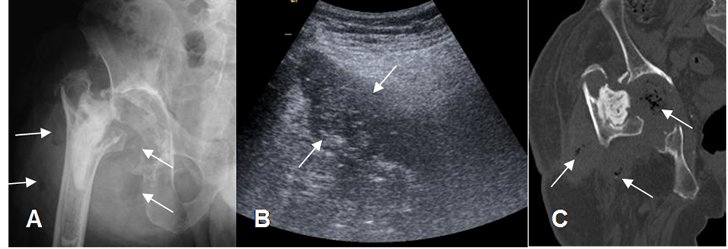

Fig 123. Colección PostQx.

A: Rx AP, B: TAC axial y C: TAC reconstrucción coronal. Colección de tejidos blandos en el PostQx temprano, después de la colocación de un reemplazo de cadera.

Fig 123 A. Infección.

A: Rx AP. Infección en la prótesis bipolar, por lo que se retira. Hay luxación de la cabeza femoral, edema de tejidos blandos y burbujas de aire. (Flechas).

B: Ecografía. Imagen redondeada y heterogénea en los tejidos blandos, que corresponde a colección.

C: TAC reconstrucción coronal. Edema de tejidos blandos y presencia de colección sobre la cavidad acetabular, con burbujas de aire. (Flechas).